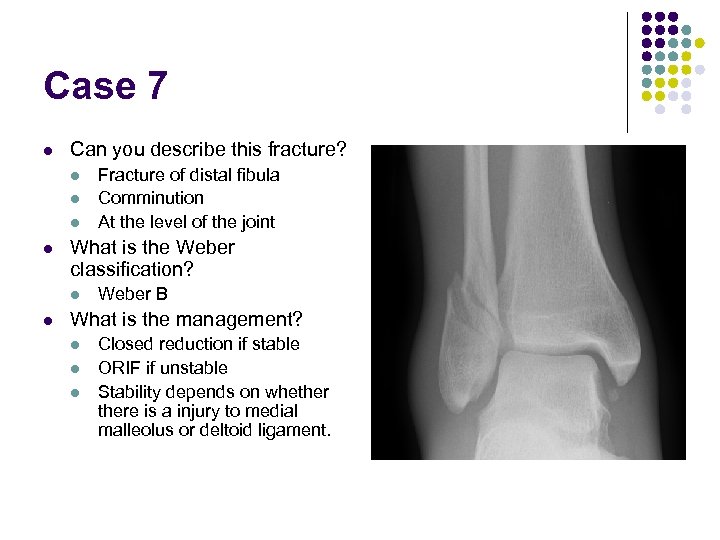

Case 7 l Can you describe this fracture? l l What is the Weber classification? l l Fracture of distal fibula Comminution At the level of the joint Weber B What is the management? l l l Closed reduction if stable ORIF if unstable Stability depends on whethere is a injury to medial malleolus or deltoid ligament.